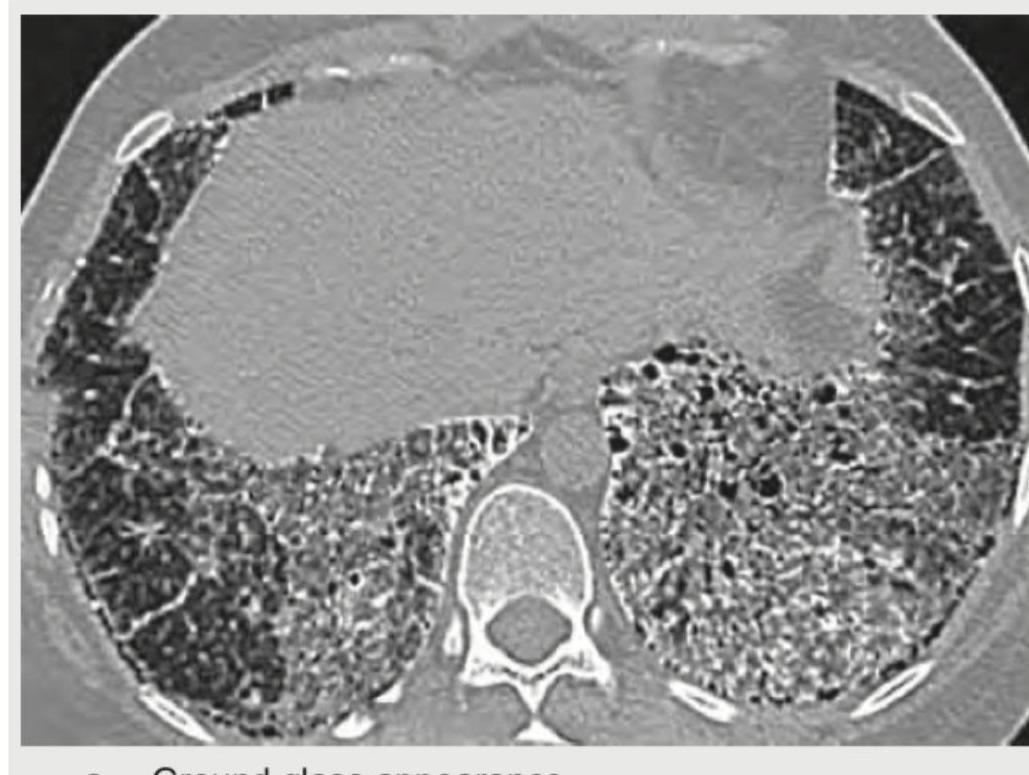

Explanation: ***Ground glass appearance*** - The image displays hazy opacification of the lung parenchyma, where **bronchial and vascular margins remain visible**. This pattern is characteristic of ground-glass opacity, indicating partial filling of air spaces or interstitial thickening. - This finding is often associated with conditions like **pneumonitis**, early acute respiratory distress syndrome (ARDS), or some atypical infections, where there's fluid or cellular infiltrates in the alveoli without complete consolidation. *Honey comb pattern* - **Honeycomb lung** is characterized by the presence of multiple cystic airspaces with thick, fibrotic walls, typically occurring in subpleural and peripheral lung regions. - This pattern signifies **end-stage pulmonary fibrosis** and is distinct from the more widespread, hazy opacification seen in the provided image. *Signet ring pattern* - The **signet ring sign** is typically observed in **bronchiectasis**, where a dilated bronchus (the "ring") is accompanied by a smaller, adjacent pulmonary artery (the "gemstone"). - This pattern indicates irreversible widening of the airways and is not represented by the diffuse hazy lung changes in the image. *Crazy pavement pattern* - **Crazy paving** refers to a combination of widespread **ground-glass opacities superimposed on thickened interlobular septa and intralobular lines**. - While the image shows ground-glass change, the prominent and widespread septal thickening required to meet the criteria for crazy paving is not clearly evident throughout the affected areas.